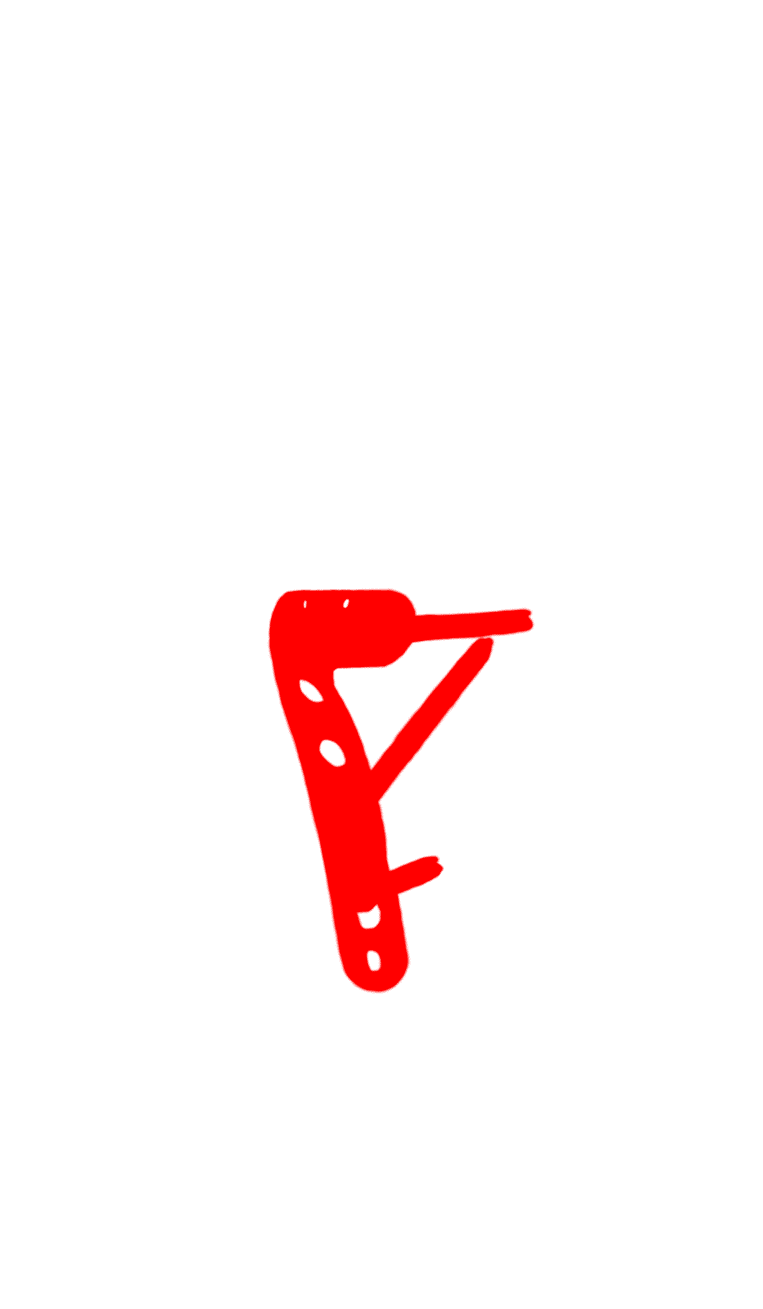

50-year-old female:

Post open reduction control of a Schatzker 2 tibial plateau fracture.

Post open reduction control of a Schatzker 2 tibial plateau fracture.

Locked plate and screws

Tibial plateau fracture

Plate and screws

Open reduction of a Schatzker 2 tibial plateau fracture and internal fixation with a locked plate and screws.